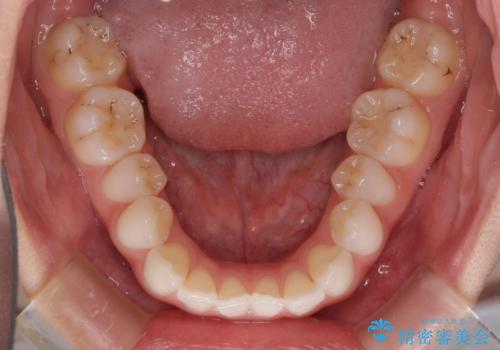

- 海外留学を前に上下のデコボコと奥歯の咬み合わせを改善したいとのことで来院された患者様です。

期間が限られていたため、ワイヤー装置による矯正治療を行うこととしました。

治療開始から4ヶ月ほどで概ね歯列が整い、その後の3ヶ月で細かい部分を仕上げていきました。

短期間で綺麗に仕上がり、患者様には大変満足していただきました。